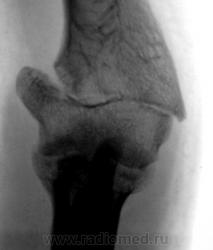

Перелом сросся наполовину (объёма повреждения), а сустав работает...

А суставная щель?

Локтевой сустав коварный, в плане выраженейших контрактур, а травма приличная, разработать будет "от сложно до невозможно".

Разрабатывает сквозь слёзы.

... - "артрозно" изменена.